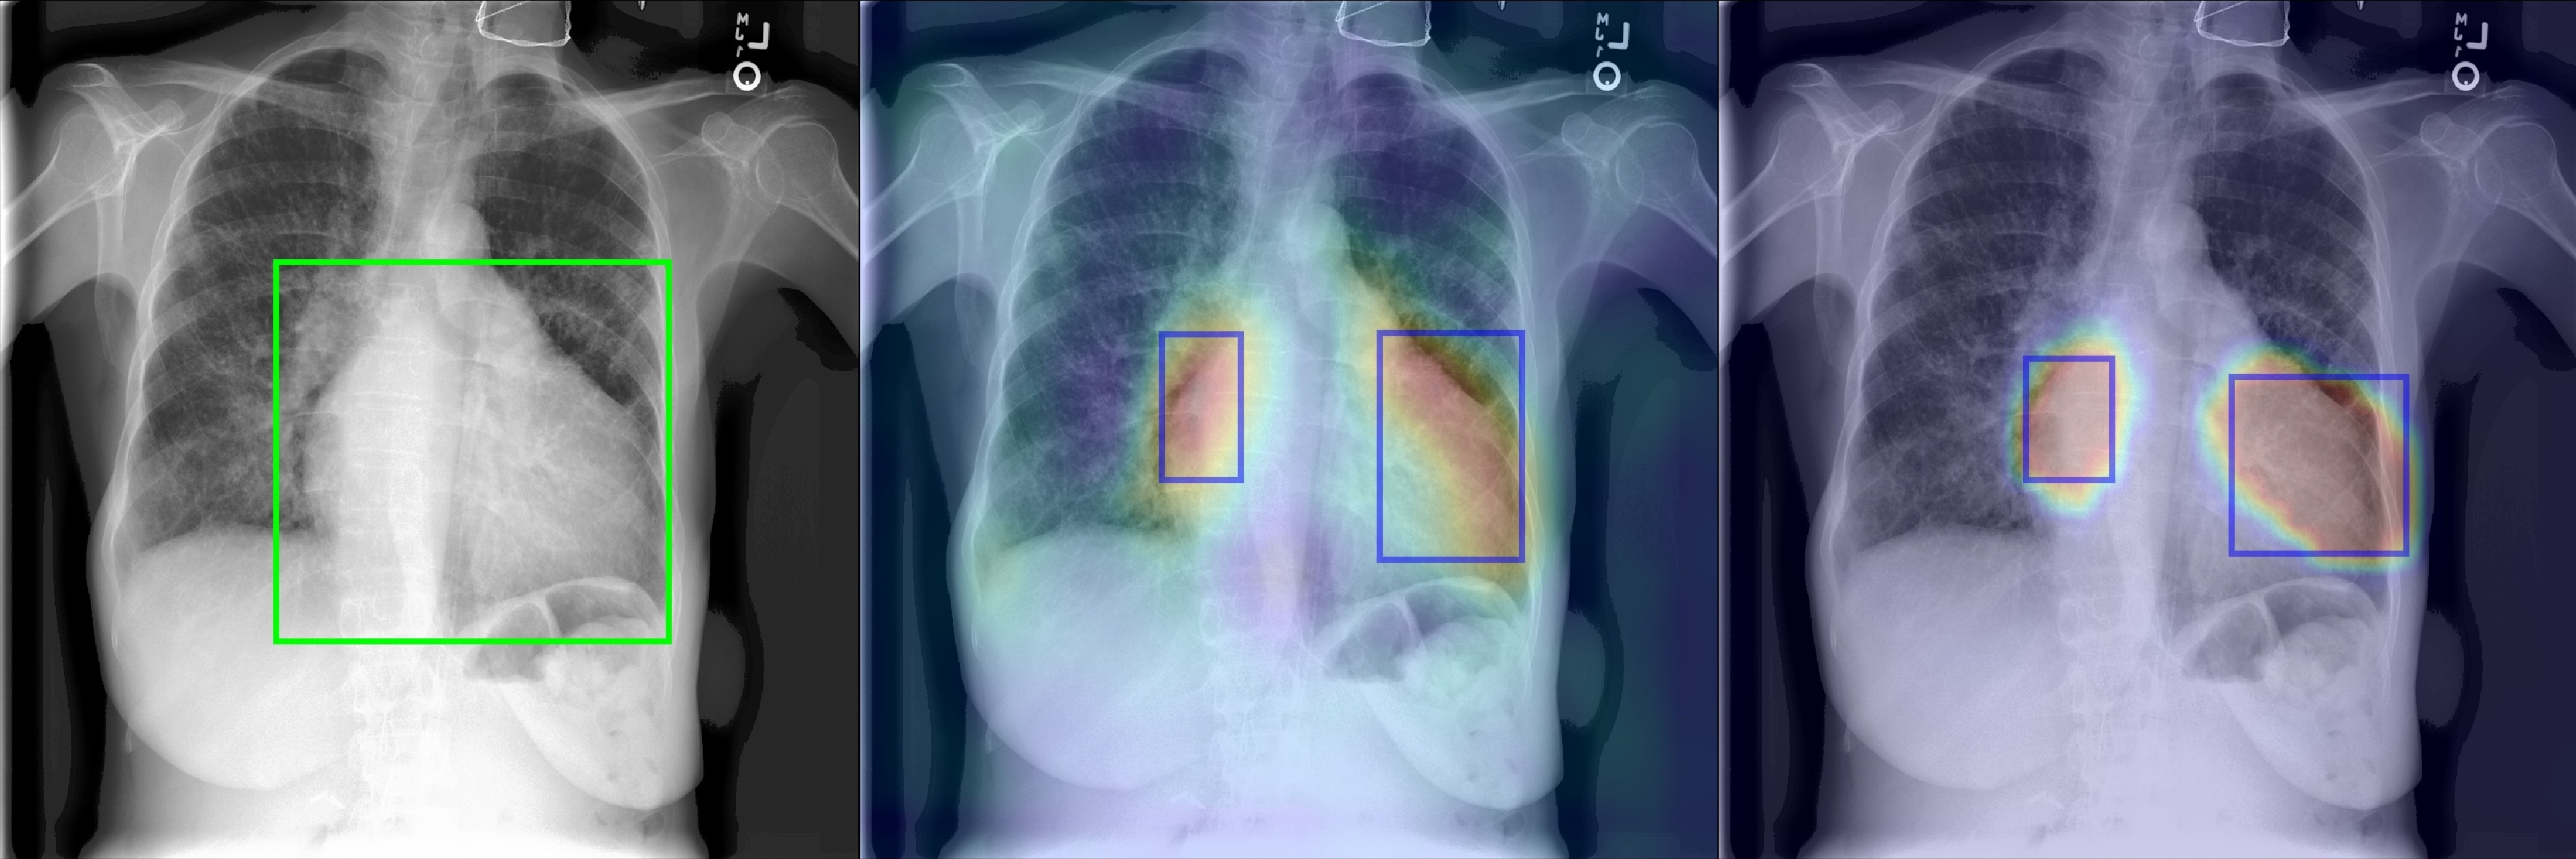

Figure 2 shows a few selected examples of the probability maps generated by PCAM pooling and the class activation maps generated by LSE pooling together with the predicted bounding boxes. Compared to the class activation maps, the probability maps are visually more clear with sharp boundaries around lesion regions. We attribute the improved visual quality to the probabilistic interpretation of the sigmoid-bounded class activation map and explicitly using it for training with global pooling.

We notice the probability maps generated by PCAM pooling tend to enlarge regions of interest in general than class activation maps from LSE pooling, especially when the ground truth regions are small, such as “Nodule” in Figure 2. This may explain the fact that PCAM pooling has relatively larger average false positives than CAM with LSE pooling.

Figure 2: Selected samples of localization heatmaps and their bounding boxes generated by LSE pooling and PCAM pooling on the test set of ChestX-ray14 [7]. In each subfigure, the left panel is the original chest X-ray with the ground truth bounding boxes (green), the middle panel is the class activation map and predicted bounding boxes (blue) by LSE pooling, the right panel is the probability map and predicted bounding boxes (blue) by PCAM pooling.